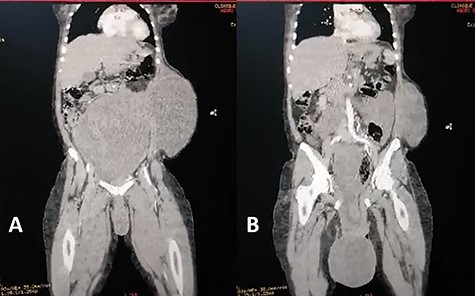

Coronal view of abdominal enhanced CT scan showing: (A) large, well-limited and slightly enhanced abdominopelvic mass. (B) protusion of the abdominopelvic mass trough perineum.